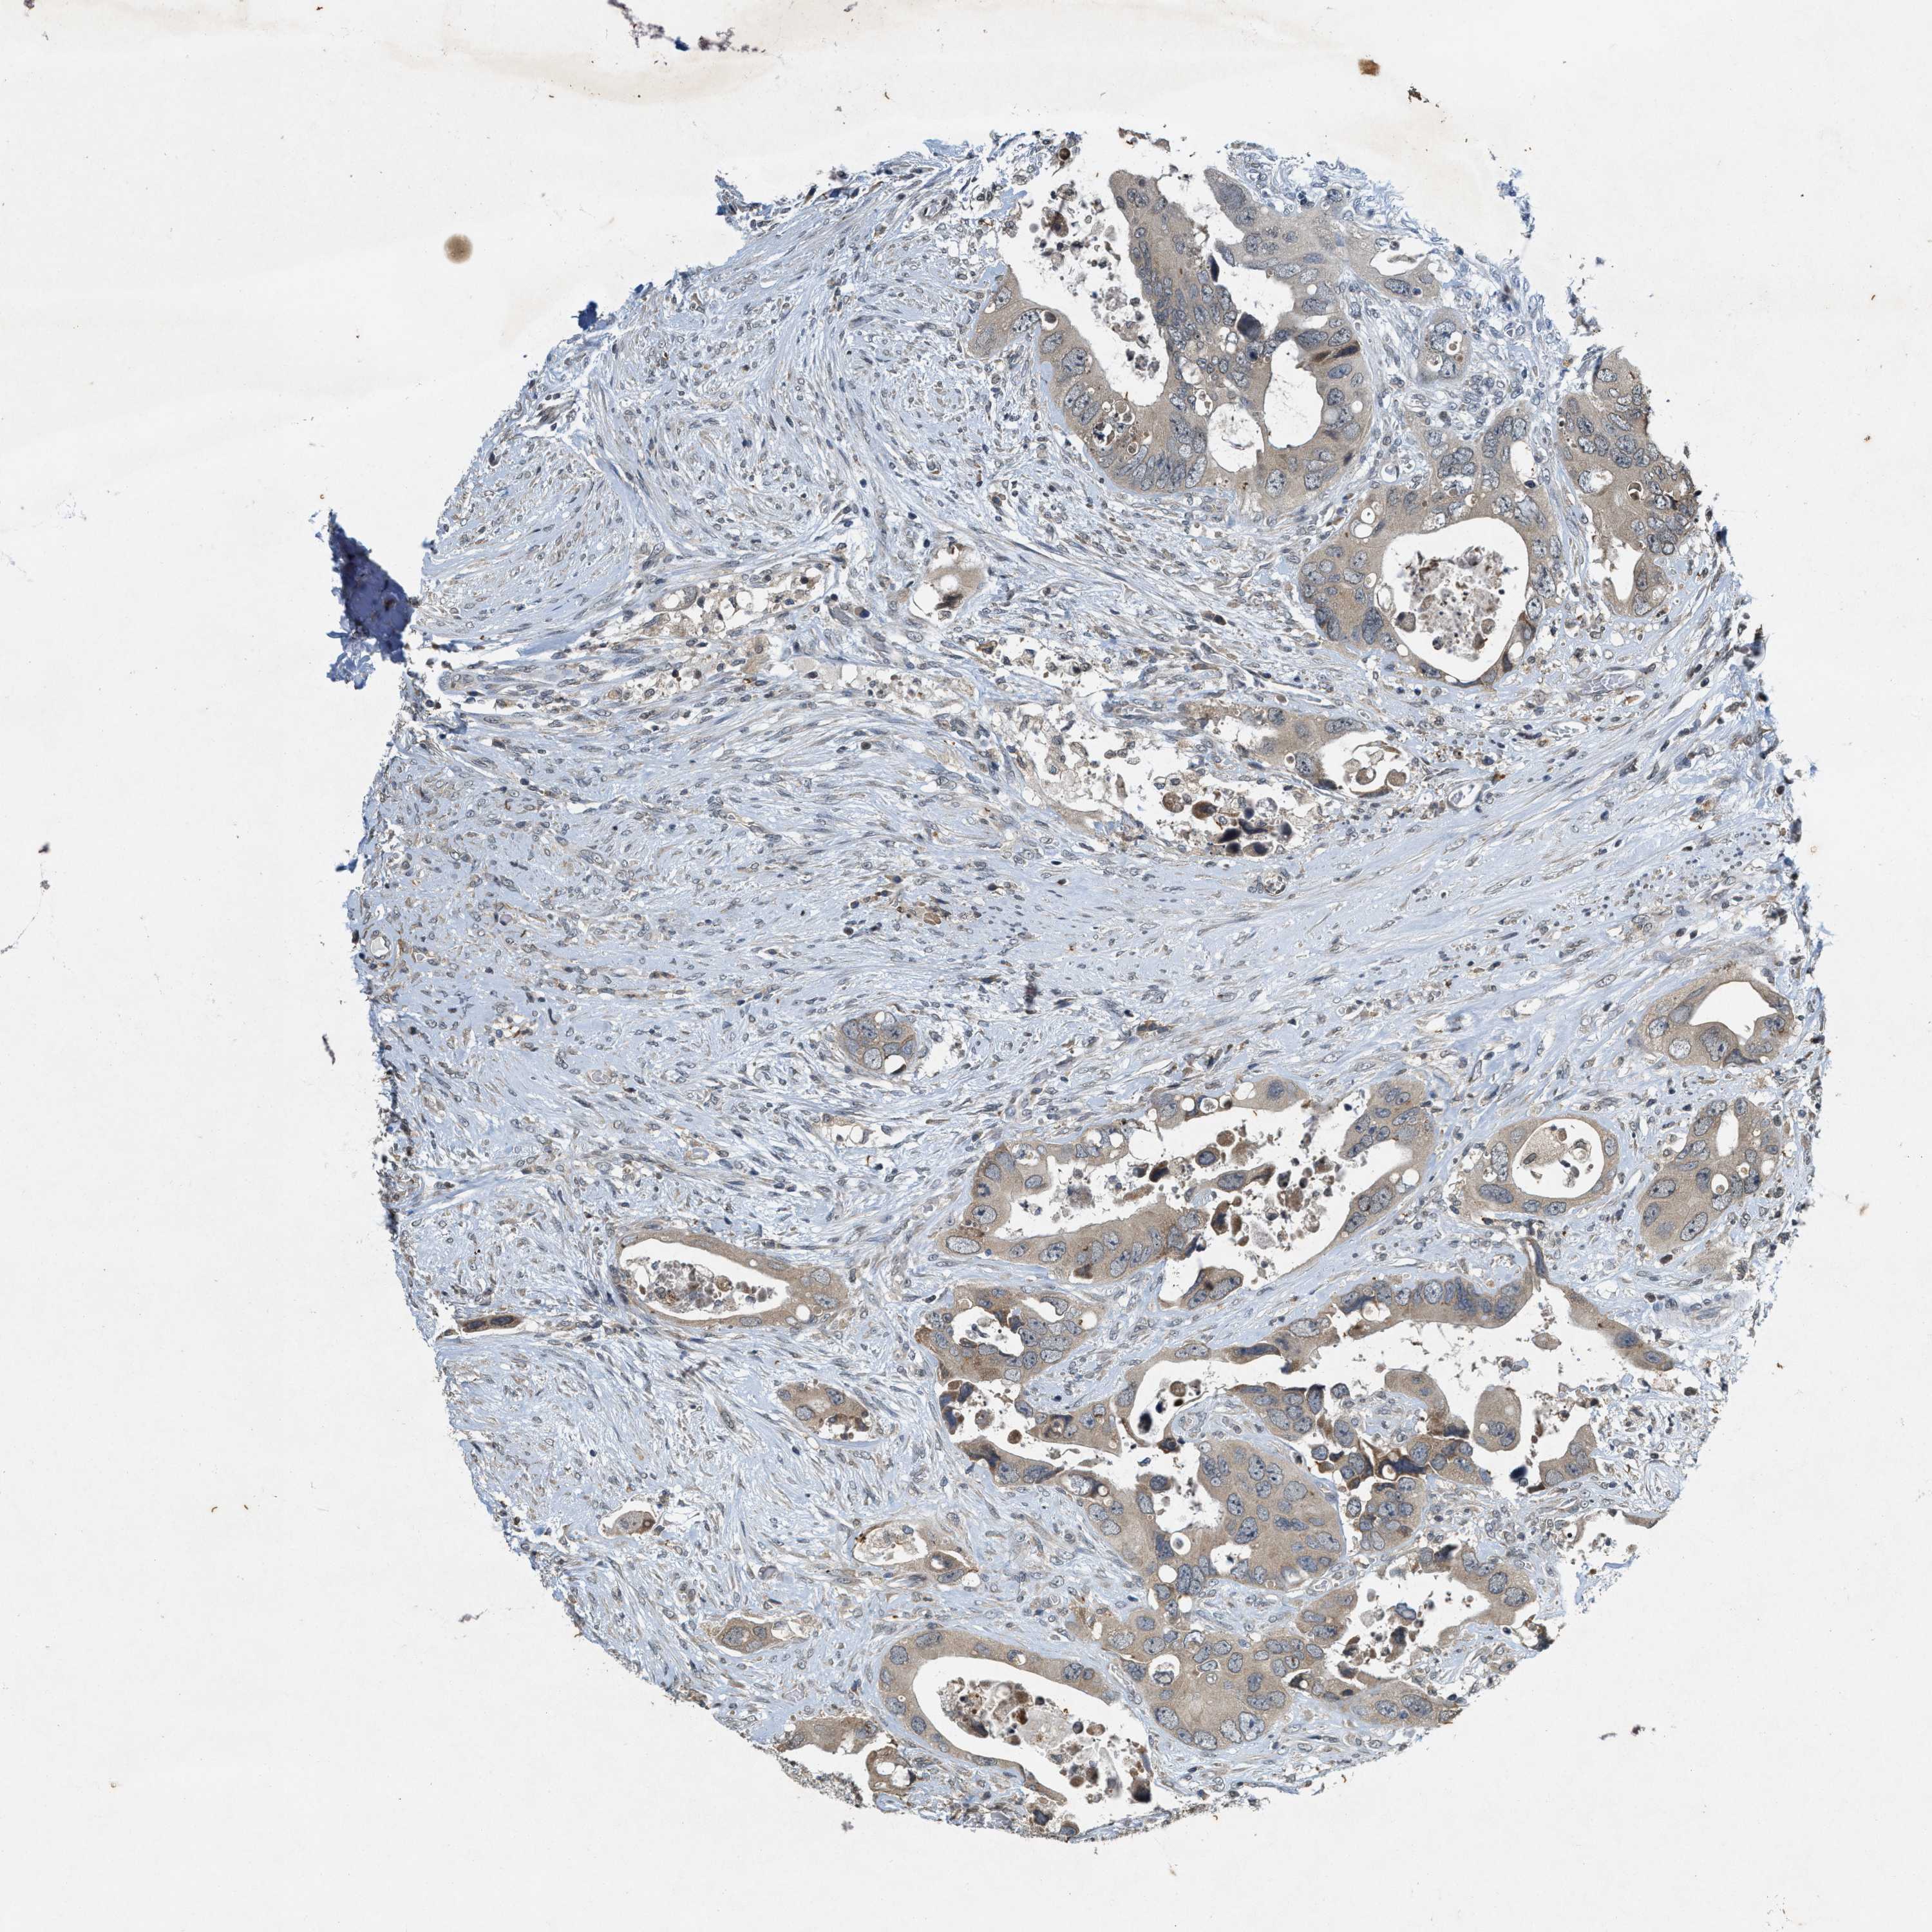

CANCER COLORECTAL CANCER Show tissue menu

Colorectal cancer

Colon adenocarcinoma